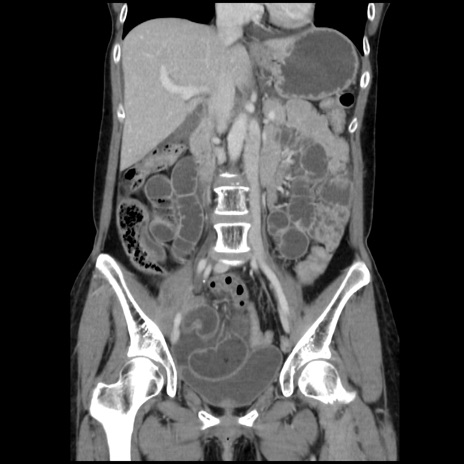

症例32(冠状断像)

【症例】40歳代 女性

【主訴】上腹部痛、嘔気・嘔吐

【現病歴】約9時間前頃から急に上腹部痛、嘔気、嘔吐が出現。改善しないため救急要請。

【既往歴】子宮頚癌(広汎子宮全摘術、放射線療法)、腸閉塞

【身体所見】腹部:平坦、軟、腸雑音亢進、上腹部を中心に腹部全体に圧痛あり。

【データ】WBC 8400、CRP 0.03